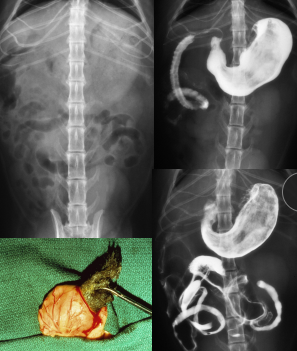

Gastroduodenal Ulcers

Et: NSAID, Steroid, GDV, MCT, renal dz, hepatic dz, sepsis

NSAIDs block PG synthesis → ↓ mucus, bicarb, blood flow → mucosal erosion

NSAID + steroid = ulcer

Cs: Hematemesis, melena, anemia, pale MM

Dt: Endoscopy (#1), regen/ iron-deficiency anemia, ↓ protein, thick mucosa

Determine GI or systemic

Tx: Fluids, (PPI) Omeprazole, Sucralfate

Gastric Foreign Bodies

Et: Obx at pylorus or intestines, Metal toxicity (zinc or lead), pressure necrosis, perforation

Post-1983 pennies contain zinc

Cs: acute vomiting, Obx

Dt: metabolic alkalosis (pyloric outflow obx), repeat rads before endoscopy

LAB: Hypochloremic, hypokalemia metabolic alkalosis with obstruction

Tx: Apomorphine (sm + smooth), endoscopic removal, Sx

Gastric Dilatation-Volvulus (GDV)

Et: Rapid distention of stomach with air + volvulus @ axis

Compression of caudal vena cava → ↓ venous return → hypovolemic shock

EMERGENCY

Sig: Old, Lg, deep chest, rapid eating, aerophagia, raised food bowls, anxiety

Cs: non-productive retching, salivation, distention, tympany, tachycardia, weak pulse, shock

Dt: R-Lateral abdominal rads, double bubble, ↑ PCV, metabolic acidosis, coagulation defects

Tx:

Initial: LRS shock fluids, O2, Gastric decompression (NG tube or trocarization), Antibiotics

Sx: Emerg Gastropexy

Prevent: Prophylactic gastropexy, slow feeding, sm meals

Gastric Neoplasia

Malignant: Adenocarcinoma (dogs), Lymphoma (cats)

Benign: Leiomyoma (dogs), Polyps (cats and dogs)

CS: Chronic vomiting, weight loss, +/- hematemesis; +/- anemia

GI bleeding, delayed gastric emptying, vomiting, anorexia, weight loss

Dx: gastroscopy, biopsy

TX: Surgical resection, chemo(lymphona)

Prognosis: poor w/ malignant